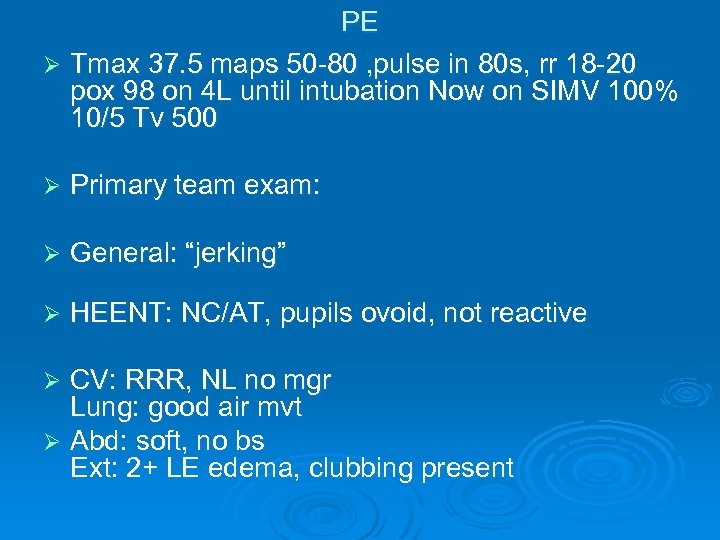

PE Ø Tmax 37. 5 maps 50 -80 , pulse in 80 s, rr 18 -20 pox 98 on 4 L until intubation Now on SIMV 100% 10/5 Tv 500 Ø Primary team exam: Ø General: “jerking” Ø HEENT: NC/AT, pupils ovoid, not reactive CV: RRR, NL no mgr Lung: good air mvt Ø Abd: soft, no bs Ext: 2+ LE edema, clubbing present Ø